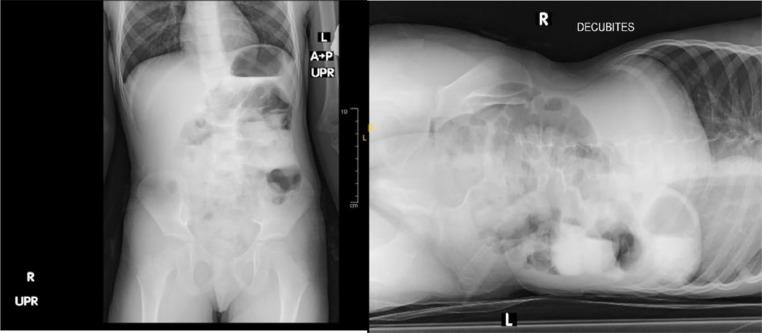

Midgut malrotations are rarely diagnosed beyond infancy. Delays in recognition and diagnosis can result in death. Here, we report the case of a 5-year-old girl who presented with a 1-year history of intermittent abdominal pain and vomiting. An abdominal computed tomography scan with contrast confirmed the diagnosis of midgut malrotation with obstruction; therefore, the Ladd procedure was performed, and the child was discharged uneventfully. Clinicians must maintain a high level of suspicion because this diagnosis is unusual in this age group.

中肠旋转不良在婴儿期之后很少被诊断出来。识别和诊断的延迟可能导致死亡。在此,我们报告一例5岁女孩的病例,她有1年间歇性腹痛和呕吐的病史。腹部增强计算机断层扫描确诊为中肠旋转不良伴梗阻;因此,实施了Ladd手术,患儿顺利出院。临床医生必须保持高度怀疑,因为这个年龄段出现这种诊断并不常见。